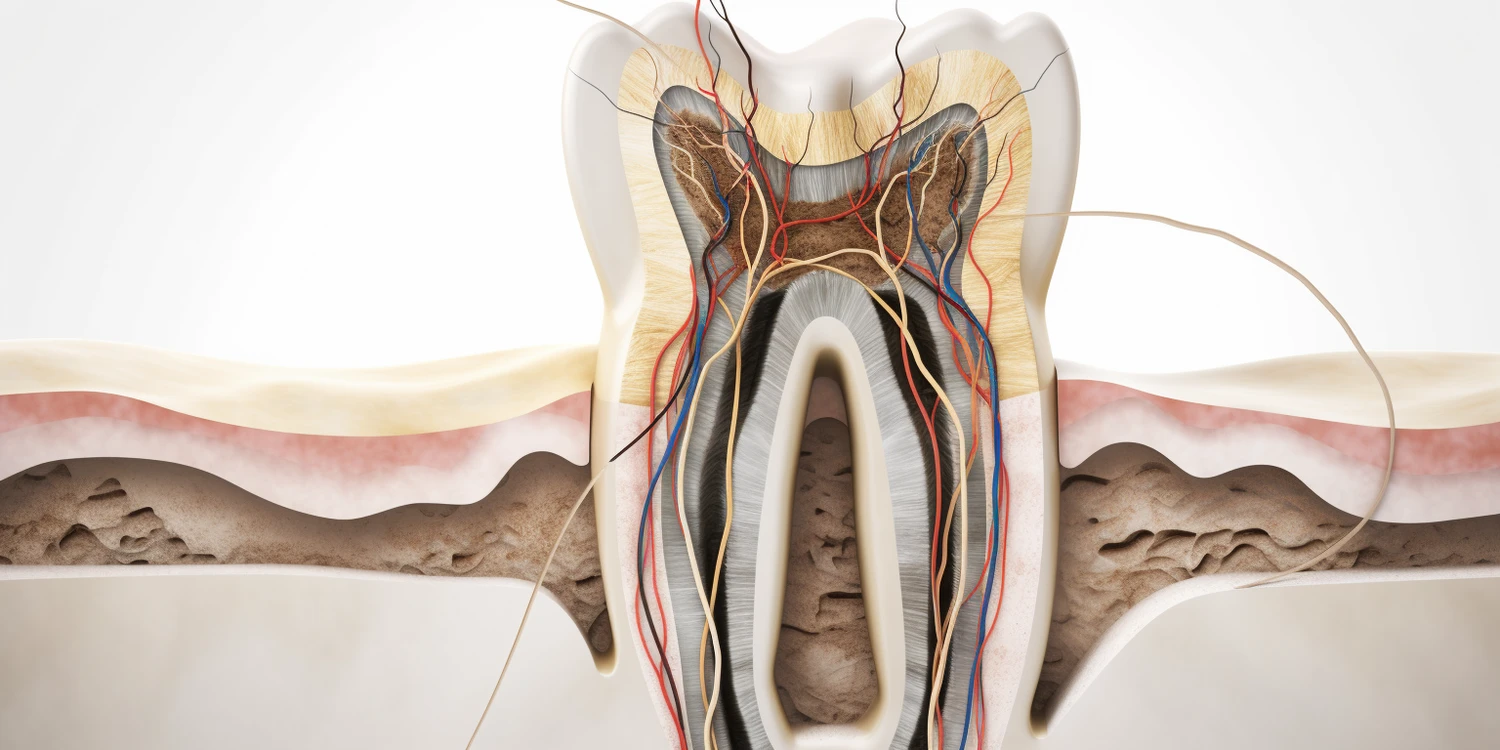

Wśród najczęstszych problemów stomatologicznych, z jakimi pacjenci zgłaszają się do stomatologa, można wymienić próchnicę, choroby dziąseł oraz nadwrażliwość zębów. Próchnica jest jednym z najpopularniejszych schorzeń jamy ustnej i dotyka zarówno dzieci, jak i dorosłych. Powstaje w wyniku działania bakterii na szkliwo zębów, co prowadzi do jego demineralizacji i powstawania ubytków. Choroby dziąseł, takie jak zapalenie dziąseł czy paradontoza, są kolejnymi powszechnymi problemami stomatologicznymi. Mogą one prowadzić do utraty zębów, jeśli nie zostaną odpowiednio leczone. Nadwrażliwość zębów to kolejny problem, który często dotyka pacjentów i objawia się bólem podczas spożywania zimnych lub gorących pokarmów. Warto podkreślić znaczenie regularnych wizyt kontrolnych u stomatologa, które pozwalają na wczesne wykrycie i leczenie tych schorzeń.

Wizyta u stomatologa zazwyczaj rozpoczyna się od wywiadu medycznego oraz oceny stanu zdrowia jamy ustnej pacjenta. Lekarz przeprowadza dokładne badanie zębów oraz dziąseł, a także może zlecić wykonanie zdjęć rentgenowskich w celu dokładniejszej diagnozy. Po ocenie stanu uzębienia stomatolog przedstawia pacjentowi zalecenia dotyczące dalszego postępowania oraz planu leczenia. W zależności od wykrytych problemów może być konieczne przeprowadzenie zabiegów takich jak wypełnienia ubytków, usunięcie zębów czy leczenie kanałowe. Warto pamiętać o tym, że stomatolodzy często stosują różne metody znieczulenia, aby zapewnić pacjentom komfort podczas zabiegów. Po zakończeniu wizyty lekarz udziela wskazówek dotyczących pielęgnacji jamy ustnej oraz zaleca regularne kontrole.

W ostatnich latach stomatologia znacznie się rozwinęła dzięki nowym technologiom, które wprowadzają innowacyjne metody leczenia oraz diagnostyki. Jednym z najważniejszych osiągnięć jest zastosowanie technologii cyfrowej w diagnostyce, na przykład skanery wewnątrzustne, które pozwalają na dokładne odwzorowanie kształtu zębów i jamy ustnej pacjenta. Dzięki temu stomatolodzy mogą tworzyć precyzyjne modele 3D, co ułatwia planowanie zabiegów oraz produkcję indywidualnych aparatów ortodontycznych czy protez. Kolejnym przełomem są lasery stomatologiczne, które umożliwiają przeprowadzanie zabiegów takich jak usuwanie próchnicy czy leczenie chorób dziąseł z minimalnym bólem i krwawieniem. Lasery pozwalają również na szybszą regenerację tkanek oraz zmniejszenie ryzyka infekcji. Warto także wspomnieć o implantach zębowych, które stały się standardem w odbudowie brakujących zębów. Nowoczesne materiały oraz techniki wszczepiania implantów zwiększają ich trwałość oraz estetykę.